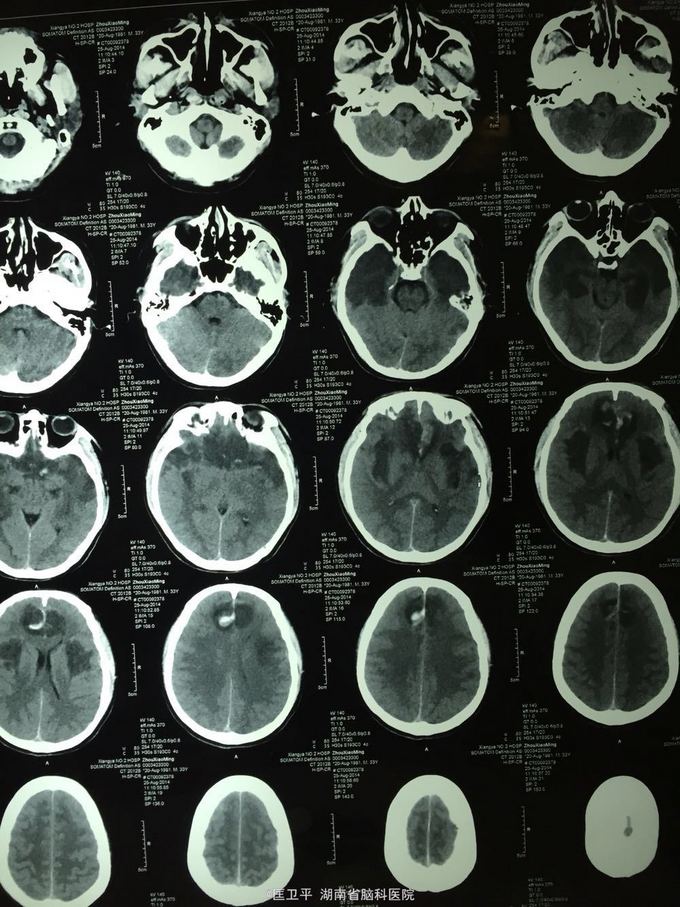

电击伤后智力低下,伤人毁物1年。 一年前在工地被电击伤昏迷,心跳呼吸停止,十几分钟后才有不规范的人工呼吸,持续约40分钟,心跳呼吸恢复。但患者智力低下,远近记忆很差,疑人害,伤人毁物严重,无法管理。

神清欠合作,五官无畸形,四肢活动正常,无神经定位体征。智能记忆很差,有被害妄想,有冲动攻击行为,无自知力,个人生活无法自理。

奥拉西坦,神经节䇞酯等护脑治疗; 丙戊酸镁、碳酸锂 稳定情绪; 奥氮平控制精神症状。 高压氧,经颅磁刺激治疗,心理治疗。